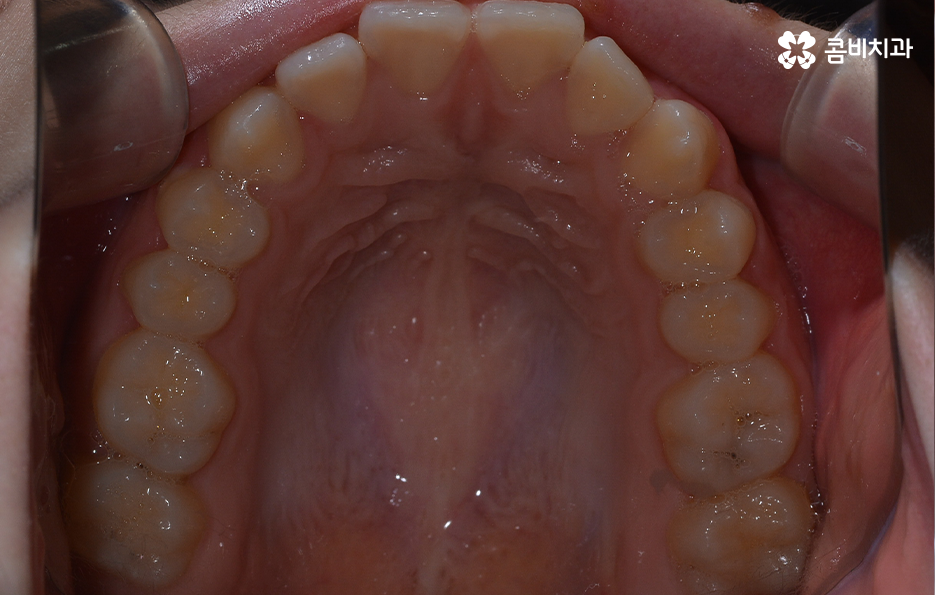

오늘 소개드릴 케이스의 경우 아랫니가 비교적 작기 때문에 교정을 통해 모아주고 윗니의 경우 측면으로 볼 때 더 잘 느껴지겠지만 다소 돌출된 상태이기 때문에 윗니는 발치를 통해 치아 이동 공간을 확보하여 돌출된 앞니를 안쪽으로 모아준 사례로 볼 수 있는데요

사진으로 보더라도 아랫니 사이가 눈에 띄게 벌어져 있는 것을 확인할 수 있어요. 보통 웃을 때는 윗니 위주로 보이긴 하지만 아랫니가 이정도로 벌어져 있는 경우에는 콤플렉스로 여겨질 수 있어요